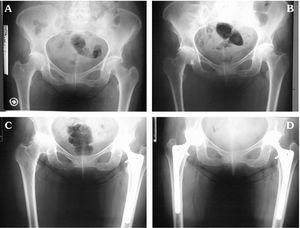

Dolor e impotencia funcional de ambas caderas

Andreu Sánchez, Sanz Sanz, Fernández Castro, Ornilla Laraudogoitia, Muñoz Carreño

Rev Clin Esp 2005;205:573-5

Fractura de cuello femoral oculta en un paciente con enfermedad de Erdheim-Chester

Ramos-Font, Rebollo Aguirre, Moral Ruiz, Bellón Guardia, Cabello García, Llamas-Elvira

Rev Esp Med Nucl Imagen Mol 2005;24:423